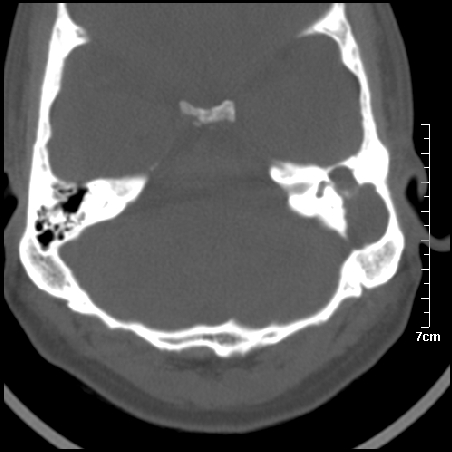

病例1

m/46y 头晕.耳鸣半月余 有乳突炎病史

左侧板障型乳突。